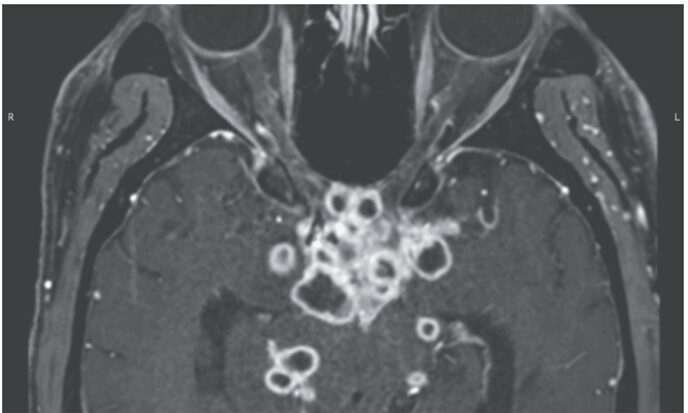

ライム病は、ボレリア菌(Borrelia burgdorferi)を保有するマダニ(Ixodes scapularis)の咬傷によって伝播する、北米などで極めて…